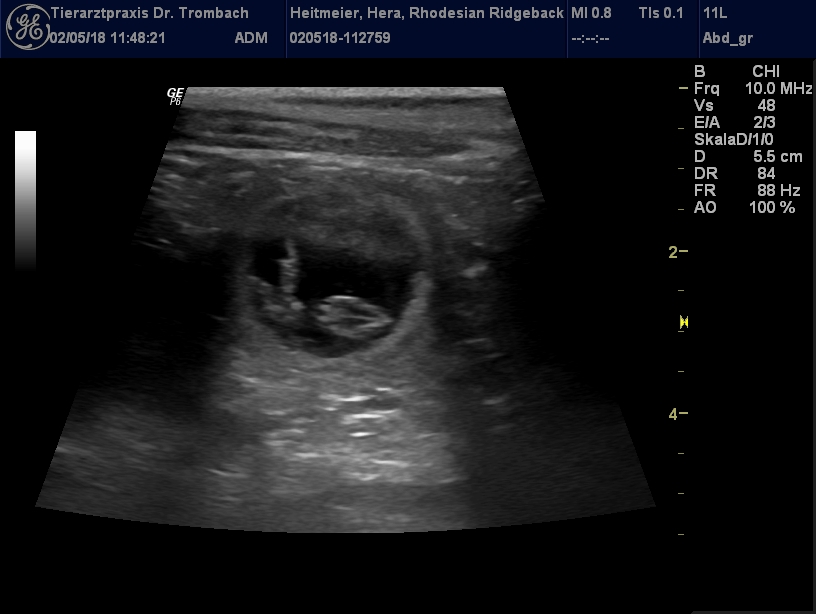

Der Ultraschall vom 02.05.2018 brachte freudige Gewissheit